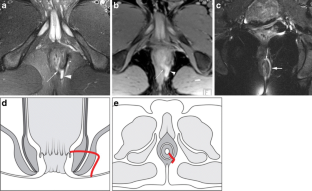

Perianal disease in pediatric Crohn disease: a review of MRI findings

Perianal complications of Crohn disease are a common occurrence in children and can result in significant morbidity when not accurately characterized prior to surgical intervention. MRI is an excellent imaging modality for the evaluation of perianal inflammatory bowel disease – allowing characterization and detailed description of perianal fistulas. MRI has many advantages over other imaging modalities for the pediatric patient. Radiologists will benefit from a sophisticated understanding of perianal anatomy, the classification of perianal fistulas, the advantages MRI offers in characterization of perianal fistulas as well as the common and incidental findings that are important in the MRI evaluation of perianal inflammatory bowel disease in children. Perianal fistulas are found at a high rate in pediatric referrals and are more commonly found in male patients.